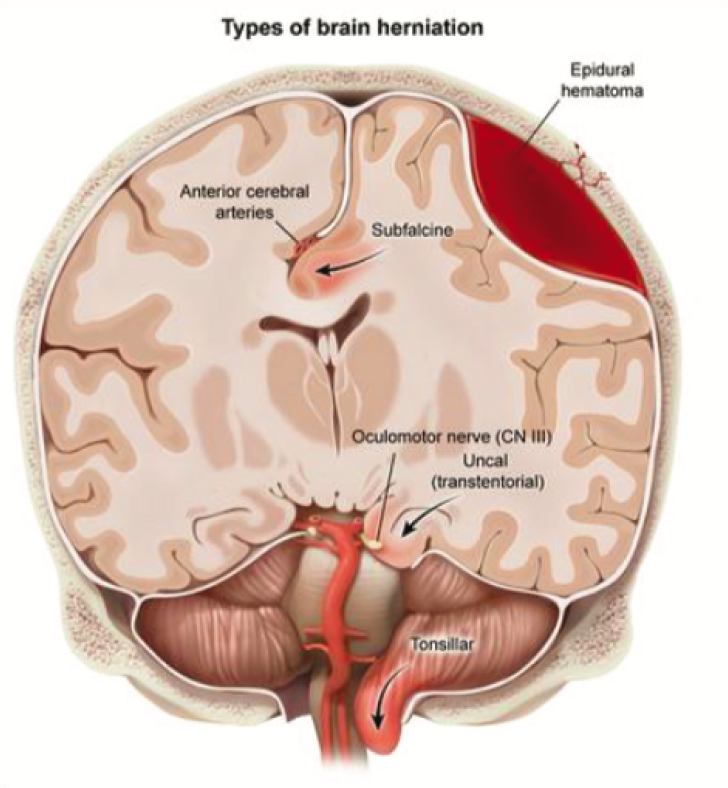

При дальнейшем геморрагическом расширении может возникнуть синдром дислокации.

Смещение мозговых структур также вызывает аномальную позу из-за нарушения нисходящих путей (например, руброспинальных, вестибулоспинальных), обычно участвующих в рефлекторных и постуральных движениях.

Вестибулоспинальный тракт поддерживает тонус разгибателей и происходит из вестибулярных ядер в понтомедуллярном соединении.

Руброспинальный тракт регулирует тонус сгибателей верхних конечностей и происходит из красных ядер в среднем мозге; он подавляется нисходящим кортикальным входом из коры головного мозга.

🚫 Повреждение над красным ядром (например, полушарие головного мозга, внутренняя капсула) обычно приводит к декортикации (сгибанию) из-за потери нисходящего торможения красного ядра и последующей гиперактивности сгибателей верхних конечностей (вариант полушарие головного мозга).

✅ Повреждение ниже красного ядра (например, моста) или самого ядра (например, среднего мозга) часто вызывает децеребральную (разгибательную) позу из-за потери нисходящего возбуждения к сгибателям верхних конечностей (через руброспинальный тракт) и преобладания разгибателей (из-за беспрепятственного выхода вестибулоспинального тракта).